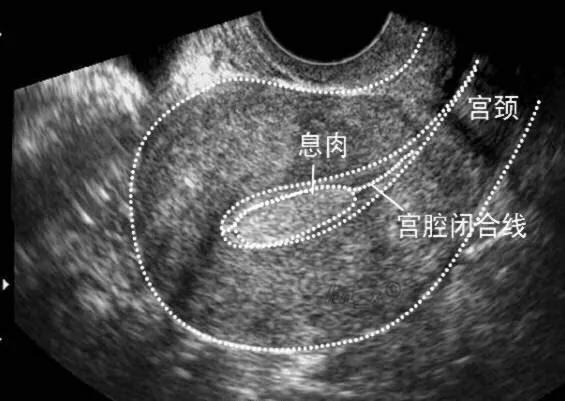

在很多月经不调、不孕症的疾病中,可以看到也值得深入评估子宫内膜容受性。比如:多囊卵巢综合征、黄体功能不足、子宫内膜异位症、子宫内膜息肉、卵巢功能减退、免疫问题等等。

2.子宫内膜异位症、内膜息肉、内膜增生过厚。实际上是相同的机制,连续而各有特点的具体表现。这些问题突出表现为雌激素偏高,或绝对值不高而相对偏高,持续黄体功能欠佳引起的孕、雄激素效应弱,无力对抗协调雌激素。不少患者在月经刚干净后内膜还是偏厚。易出现盆腔瘀血综合征、经前期头痛、腹部腰部酸胀痛、口腔溃疡、情绪差。直接引起在黄体期内膜转化不足,质地差,容受性差。